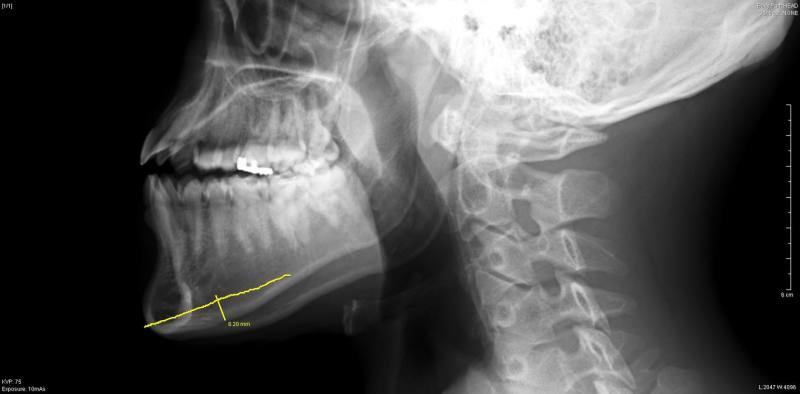

当院では、手術にあたり、

提携病院でレントゲン写真撮影を

事前に行っていただき、

切除可能な量を計測しています。

先端で6mm幅、

最大8mm幅で切除を行いました。

頭蓋側面のレントゲン写真では、

下顎骨の中央から、

先端にかけて幅が広くなっているのがわかります

骨切りのデザインの際には、

骨切りの断端をなめらかにするために、

切り始めをそこに置くことにしました。